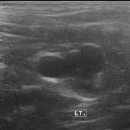

• 유스동물병원 | 전주 익산 고양이 건강검진 <유스동물병원> _검진일 2025. 5. 10.(토)

익산 유스동물병원_ 고양이 건강검진 ​ 익산 ‘유스동물병원’에서 비노의 건강검진을 받았어요! 지난 5월에 다녀왔는데 후기를 쓰는 데 거의 3개월이 걸렸네요..ㅎㅎ ​ 2025. 5. 10.(토)에 건강검진을 받았고 결과 리포트는 14일에 받았답니다. 비노가 건강검진을 받을 즈음에 동물 병원 오픈 이벤트로 건강검진 비용...

LOVE WHAT YOU DO(2025-07-27 23:18:00)